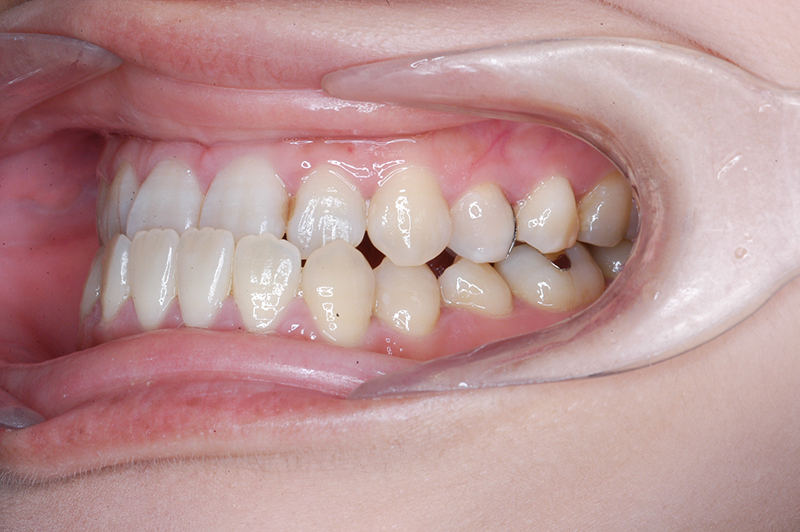

初診時

主訴 受け口 診断名 アングルⅢ級反対咬合症例

初診時年齢 31歳6ヵ月 性別 動的治療期間 15ヵ月

口腔内所見 臼歯関係はⅢ級、下顎歯列はスピーカーブによって前歯は舌側へ倒れこみつつ挺出しておりover jet-2.5mm、over bite3.0mmと反対咬合を呈していた。

批評・予后 ロウアングルのSkeletal Ⅲ級であり、下顎臼歯は近心傾斜しつつ7遠心部にはアップライトができるスペースがあると判断して、MEAWによる咬合平面の平坦化および可及的な下顎のカウンタークロックワイズローテーションによって改善を行うこととした。治療後には歯列の整直とⅠ級の咬合が得られた。(H30年9月現在で)保定開始4年経過しているが現在も咬合は安定している。